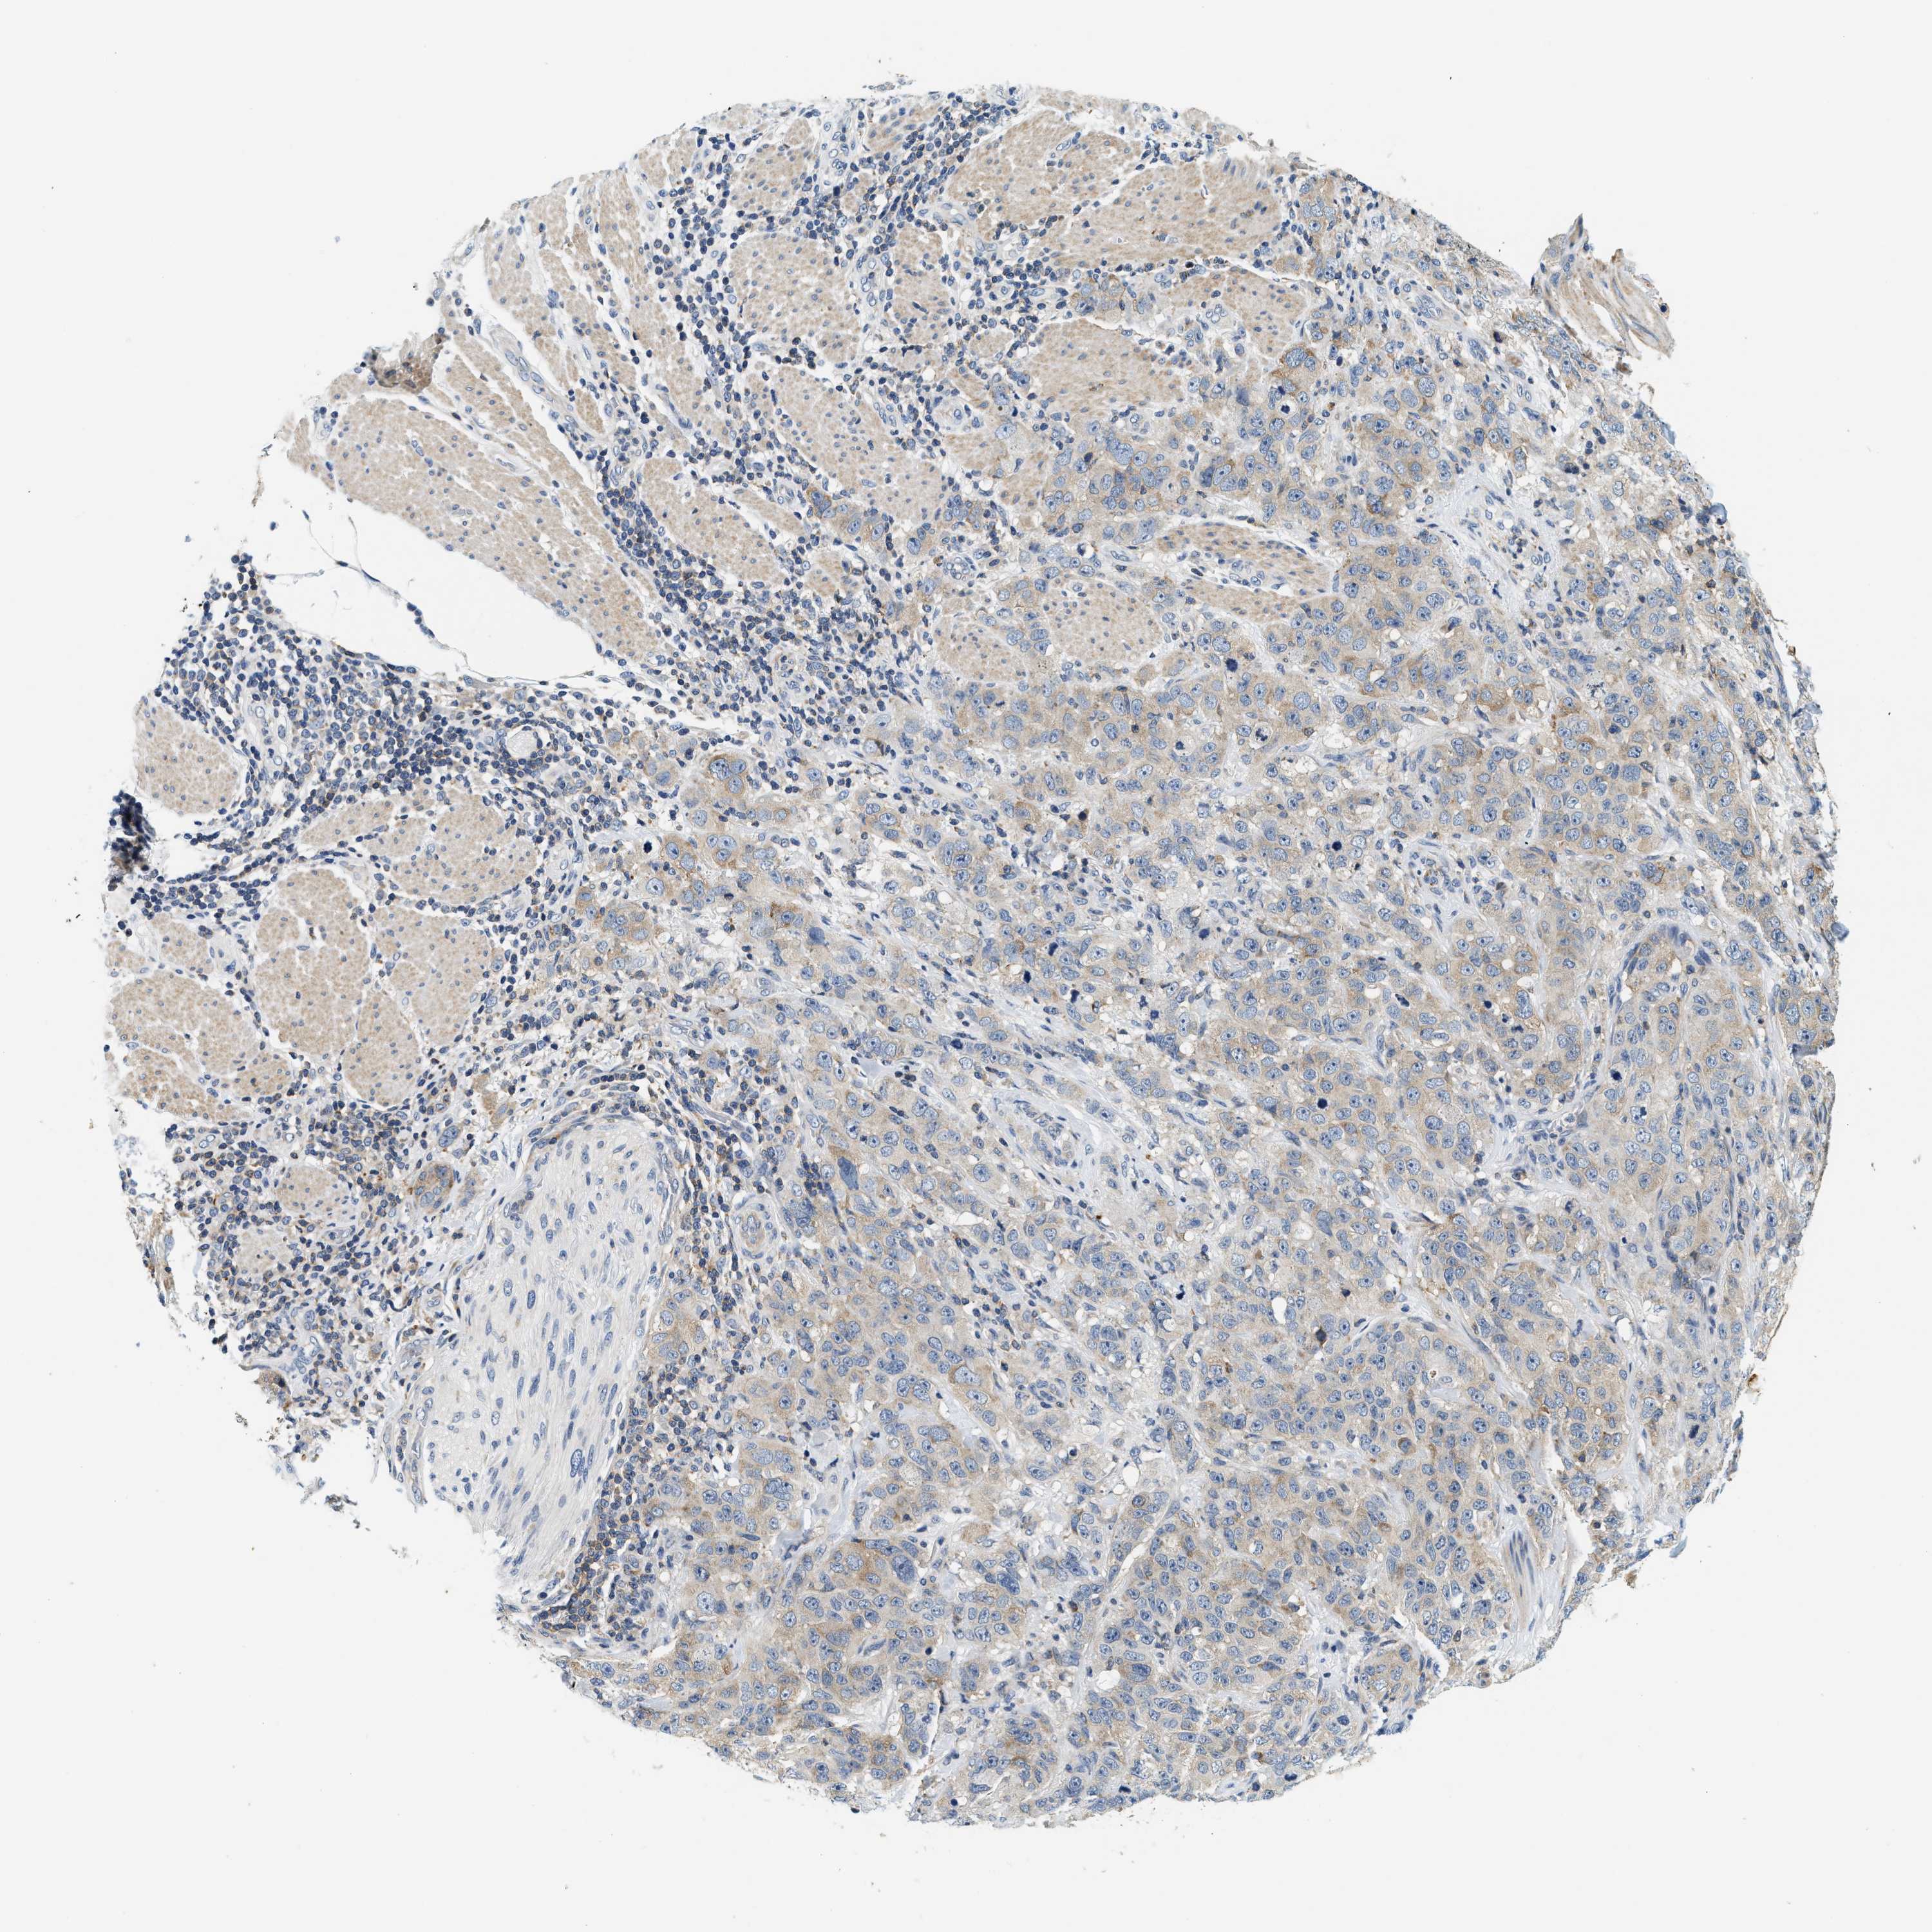

STOMACH CANCER - Protein expressioni

A mouse-over function shows sample information and annotation data. Click on an image to view it in a full screen mode. Samples can be filtered based on level of antibody staining by selecting one or several of the following categories: high, medium, low and not detected. The assay and annotation is described here.

Note that samples used for immunohistochemistry by the Human Protein Atlas do not correspond to samples in the TCGA dataset.

Antibody stainingi

Antibody staining in the annotated cell types in the current human tissue is reported as not detected, low, medium, or high, based on conventional immunohistochemistry profiling in selected tissues. This score is based on the combination of the staining intensity and fraction of stained cells.

Each image is clickable and will lead to virtual microscopy that enables deeper exploration of all samples and also displays staining intensity scores, fraction scores and subcellular localization as well as patient and tissue information for each sample.

Antibody HPA021318

Antibody HPA021319

Staining

High

Medium

Low

Not detected

Intensity

Strong

Moderate

Weak

Negative

Quantity

>75%

75%-25%

<25%

None

Location

Nuclear

Cytoplasmic/membranous

Cytoplasmic/membranous,nuclear

Adenocarcinoma, NOS